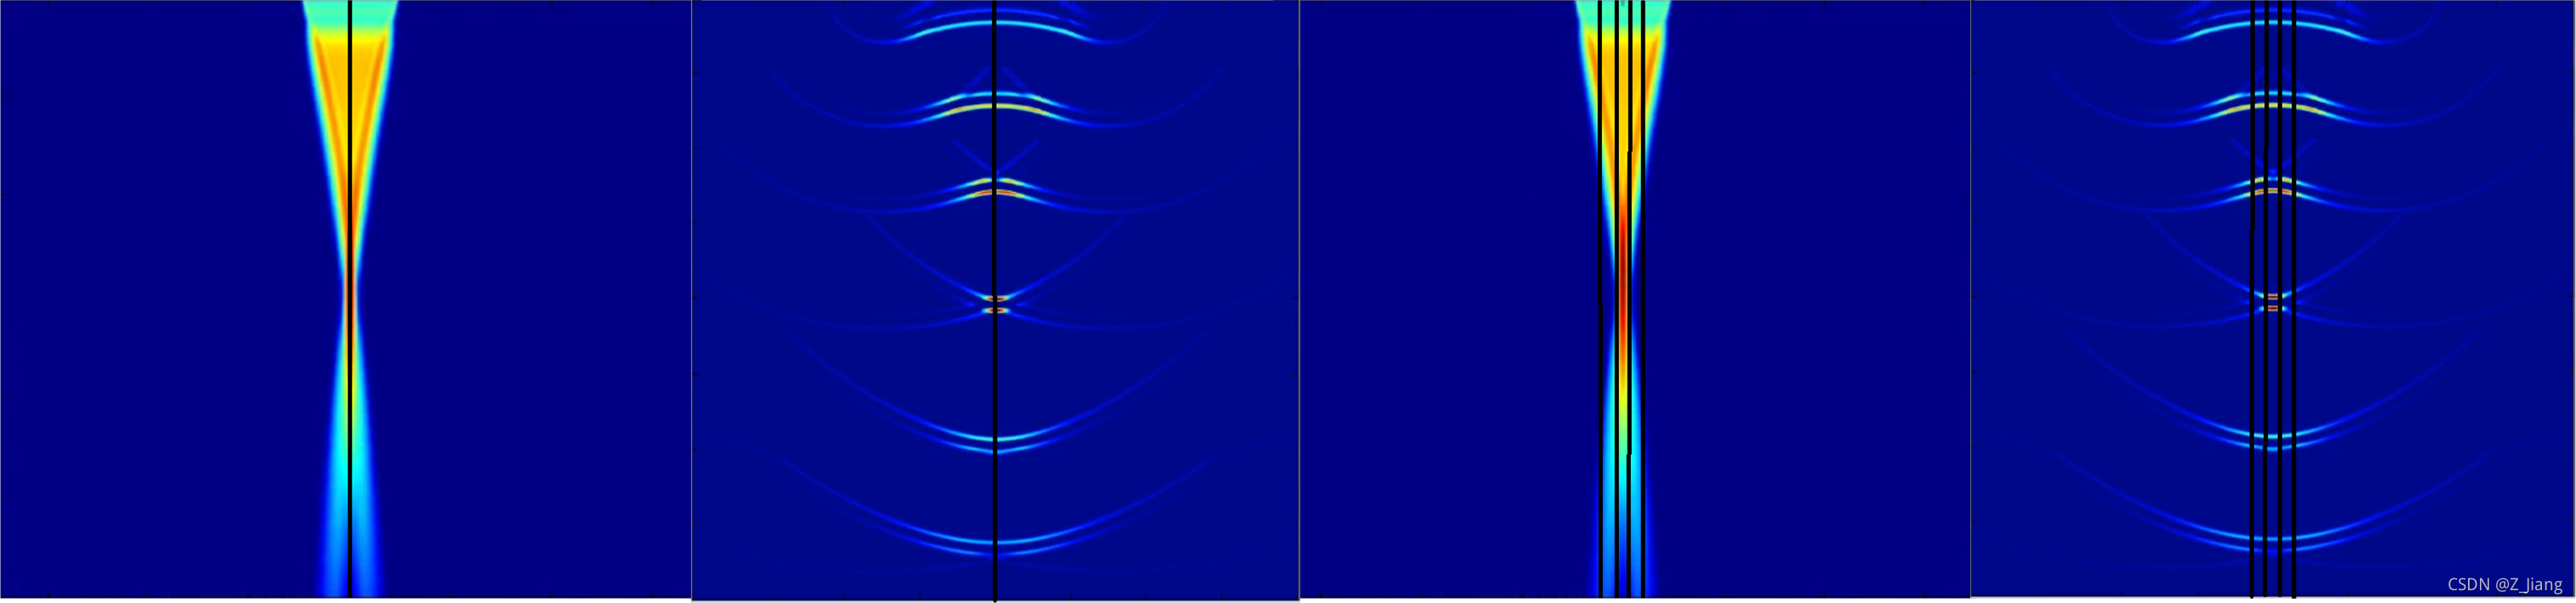

如果视频点不开,就看图吧,从左看到右,靠脑补动起来

我的声场仿真不动的画

这组仿真,是一个64阵元的小探头(按常规的相控阵配置的),声场区域长宽都是4厘米,发射聚焦在2厘米的深度,2个Cycle的激励,2MHz的发射频率。实际上声场本身是机械波的传播过程,在传播过程中会与组织发生交互,在各个位置上不断发生反射,折射,散射,衍射。上面大家看到的声场中,没有任何反射等交互,是因为我们仿真的是在水中传播的情况,没有任何的物质。但我们可以看到,由于控制了发射延迟,让所有的阵元的声波同时到达2厘米处,在2厘米处波束很窄很集中,在焦点前后逐渐远离发射焦点的地方,波束逐渐变宽。

上排:NO MLA(MLA=1) 下排:MLA=4

我们可以看到MLA=4,在相对运动时,靶点明显忽宽忽窄,扭来扭去,这就是我上面提到的第二点,也经常叫做MLA block artifact;而在MLA=1,在相对运动时,靶点时稳定的(除了在探头边上,由于接收孔径不对称造成少量轻微扭曲);